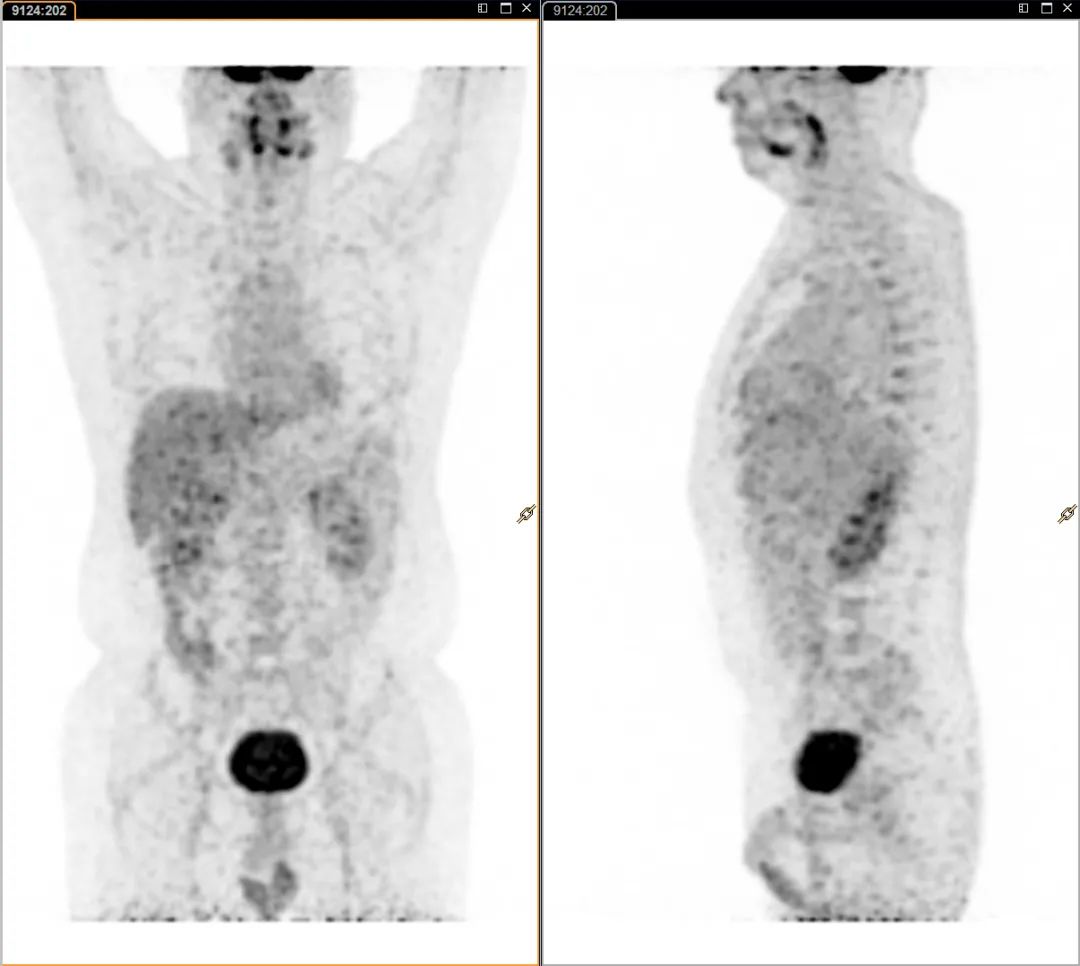

按临床医生要求,为了赶紧明确诊断,张先生到天津全景尽快进行PET/CT检查。

天津全景的影像医生仔细对比了本次CT影像与既往影像检查资料,发现病灶形态一年来没有明显变化,结合PET扫描SUV值较低且无明显代谢增高的情况,初步判断这是一个偏良性的病变。

按照天津全景“三级审核”制度,考虑临床意见全景又邀请天津三甲医院胸部影像权威的专家进行讨论会诊,结论得到了支持,考虑“良性瘤样增生”。